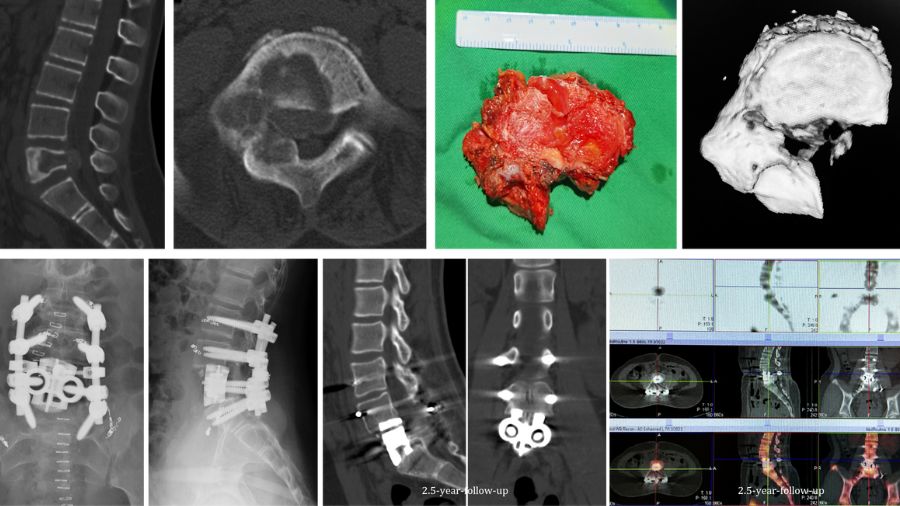

In another case, an 11 years-old girl was diagnosed with L5 osteoblastoma by CT guided biopsy. Because the tumor invaded the whole L5 vertebral body and the right facet joint and invaded posterior cortex into epidural space forming a soft tissue, it was diagnosed as Enneking S3.

The en bloc spondylectomy was undertaken by posterior approach. Postoperative gross specimen and pathological examination showed negative margin. The tumor showed no recurrence in the 2.5-year-follow-up.